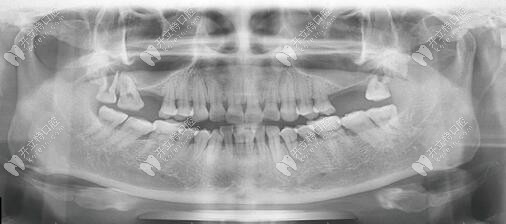

本院手術(shù)網(wǎng)友分享